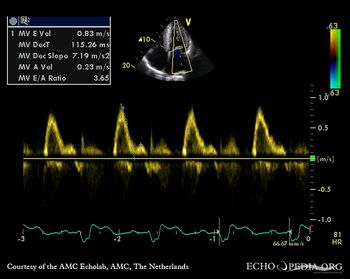

Pulsed-wave Doppler signal: restrictive pattern of mitral inflow